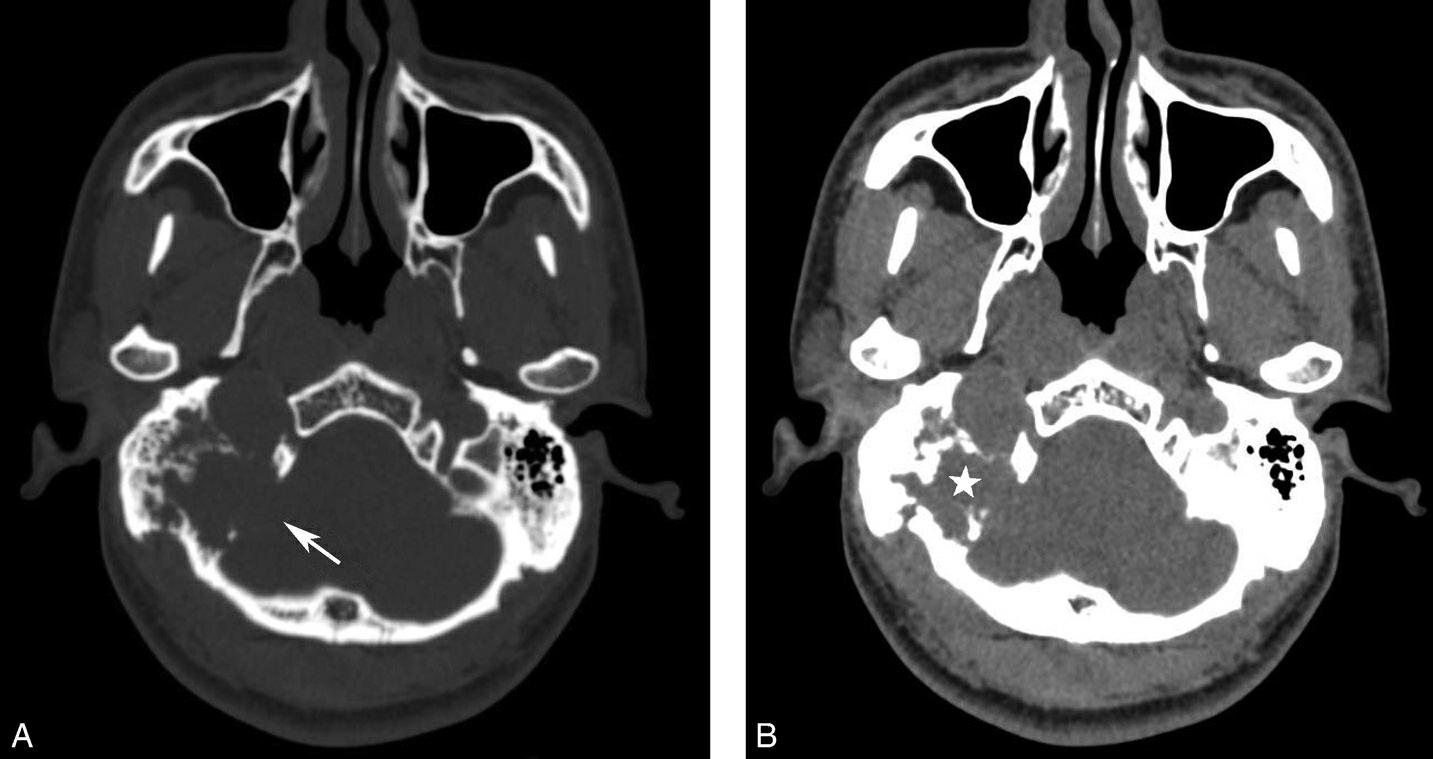

破裂孔、卵圆孔、棘孔及斜坡等均为重要的解剖结构,临床常见疾病如鼻咽癌常侵犯上述结构(图1-2-3)。颈静脉孔区较常见的肿瘤为颈静脉球瘤,常伴有颈静脉孔及其邻近骨质的破坏(图1-2-4)。

图1-2-3 鼻咽癌颅底骨质破坏

A.横断面;B.横断面(骨窗)

骨窗示左侧岩尖、斜坡、左侧蝶骨大翼骨质破坏、受侵(白箭),肿瘤经破裂孔侵入颅内(黑箭头)

图1-2-4 右侧颈静脉球瘤

A.横断面(骨窗);B.横断面

右侧颈静脉孔区不规则骨质破坏(箭),局部见软组织肿块(☆)